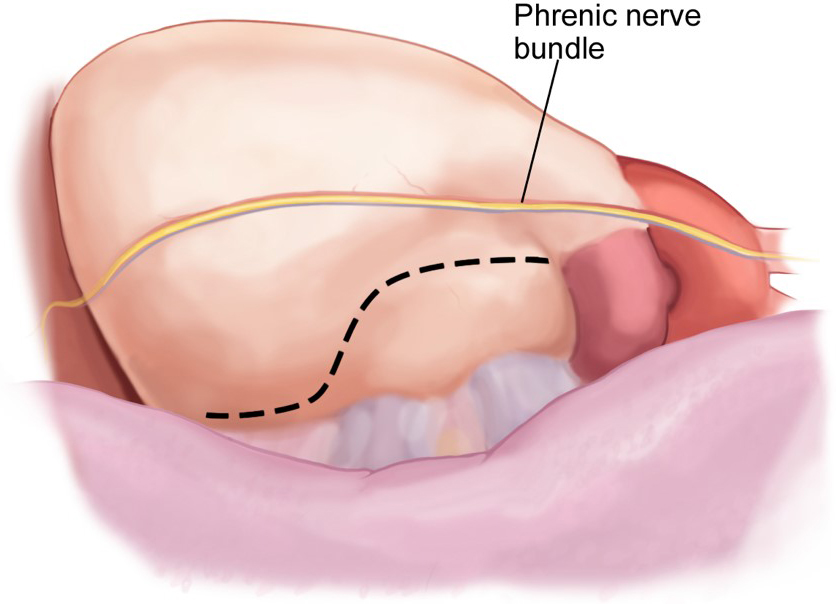

If a concomitant appendage ligation is to be performed, the left lung is then

deflated, and the TEE probe is reinserted. Again, the details of this portion

have been previously well defined [14, 15] and will be only briefly reviewed for

relevant pitfalls and controversial points. The phrenic nerve should be clearly

identified, and the pericardium opened most commonly posterior to its course

(Fig. 4). Caution should be used as the confluence of the PA and the pericardium

is approached to avoid injury to this major vessel. Some surgeons will at this

time ablate the Ligament of Marshall which lies here in the transverse sinus and

may be easily obliterated with the use of vessel-sealing or ultrasonic energy

devices. Once the base of the appendage is sized, the clip is advanced through

the most inferior and posterior port. After the clip has been applied to the base

of the appendage, an inspection in several views with TEE confirms a

Fig. 4.

Fig. 4.Left atrial appendage access via a Left VATS pericardiotomy.